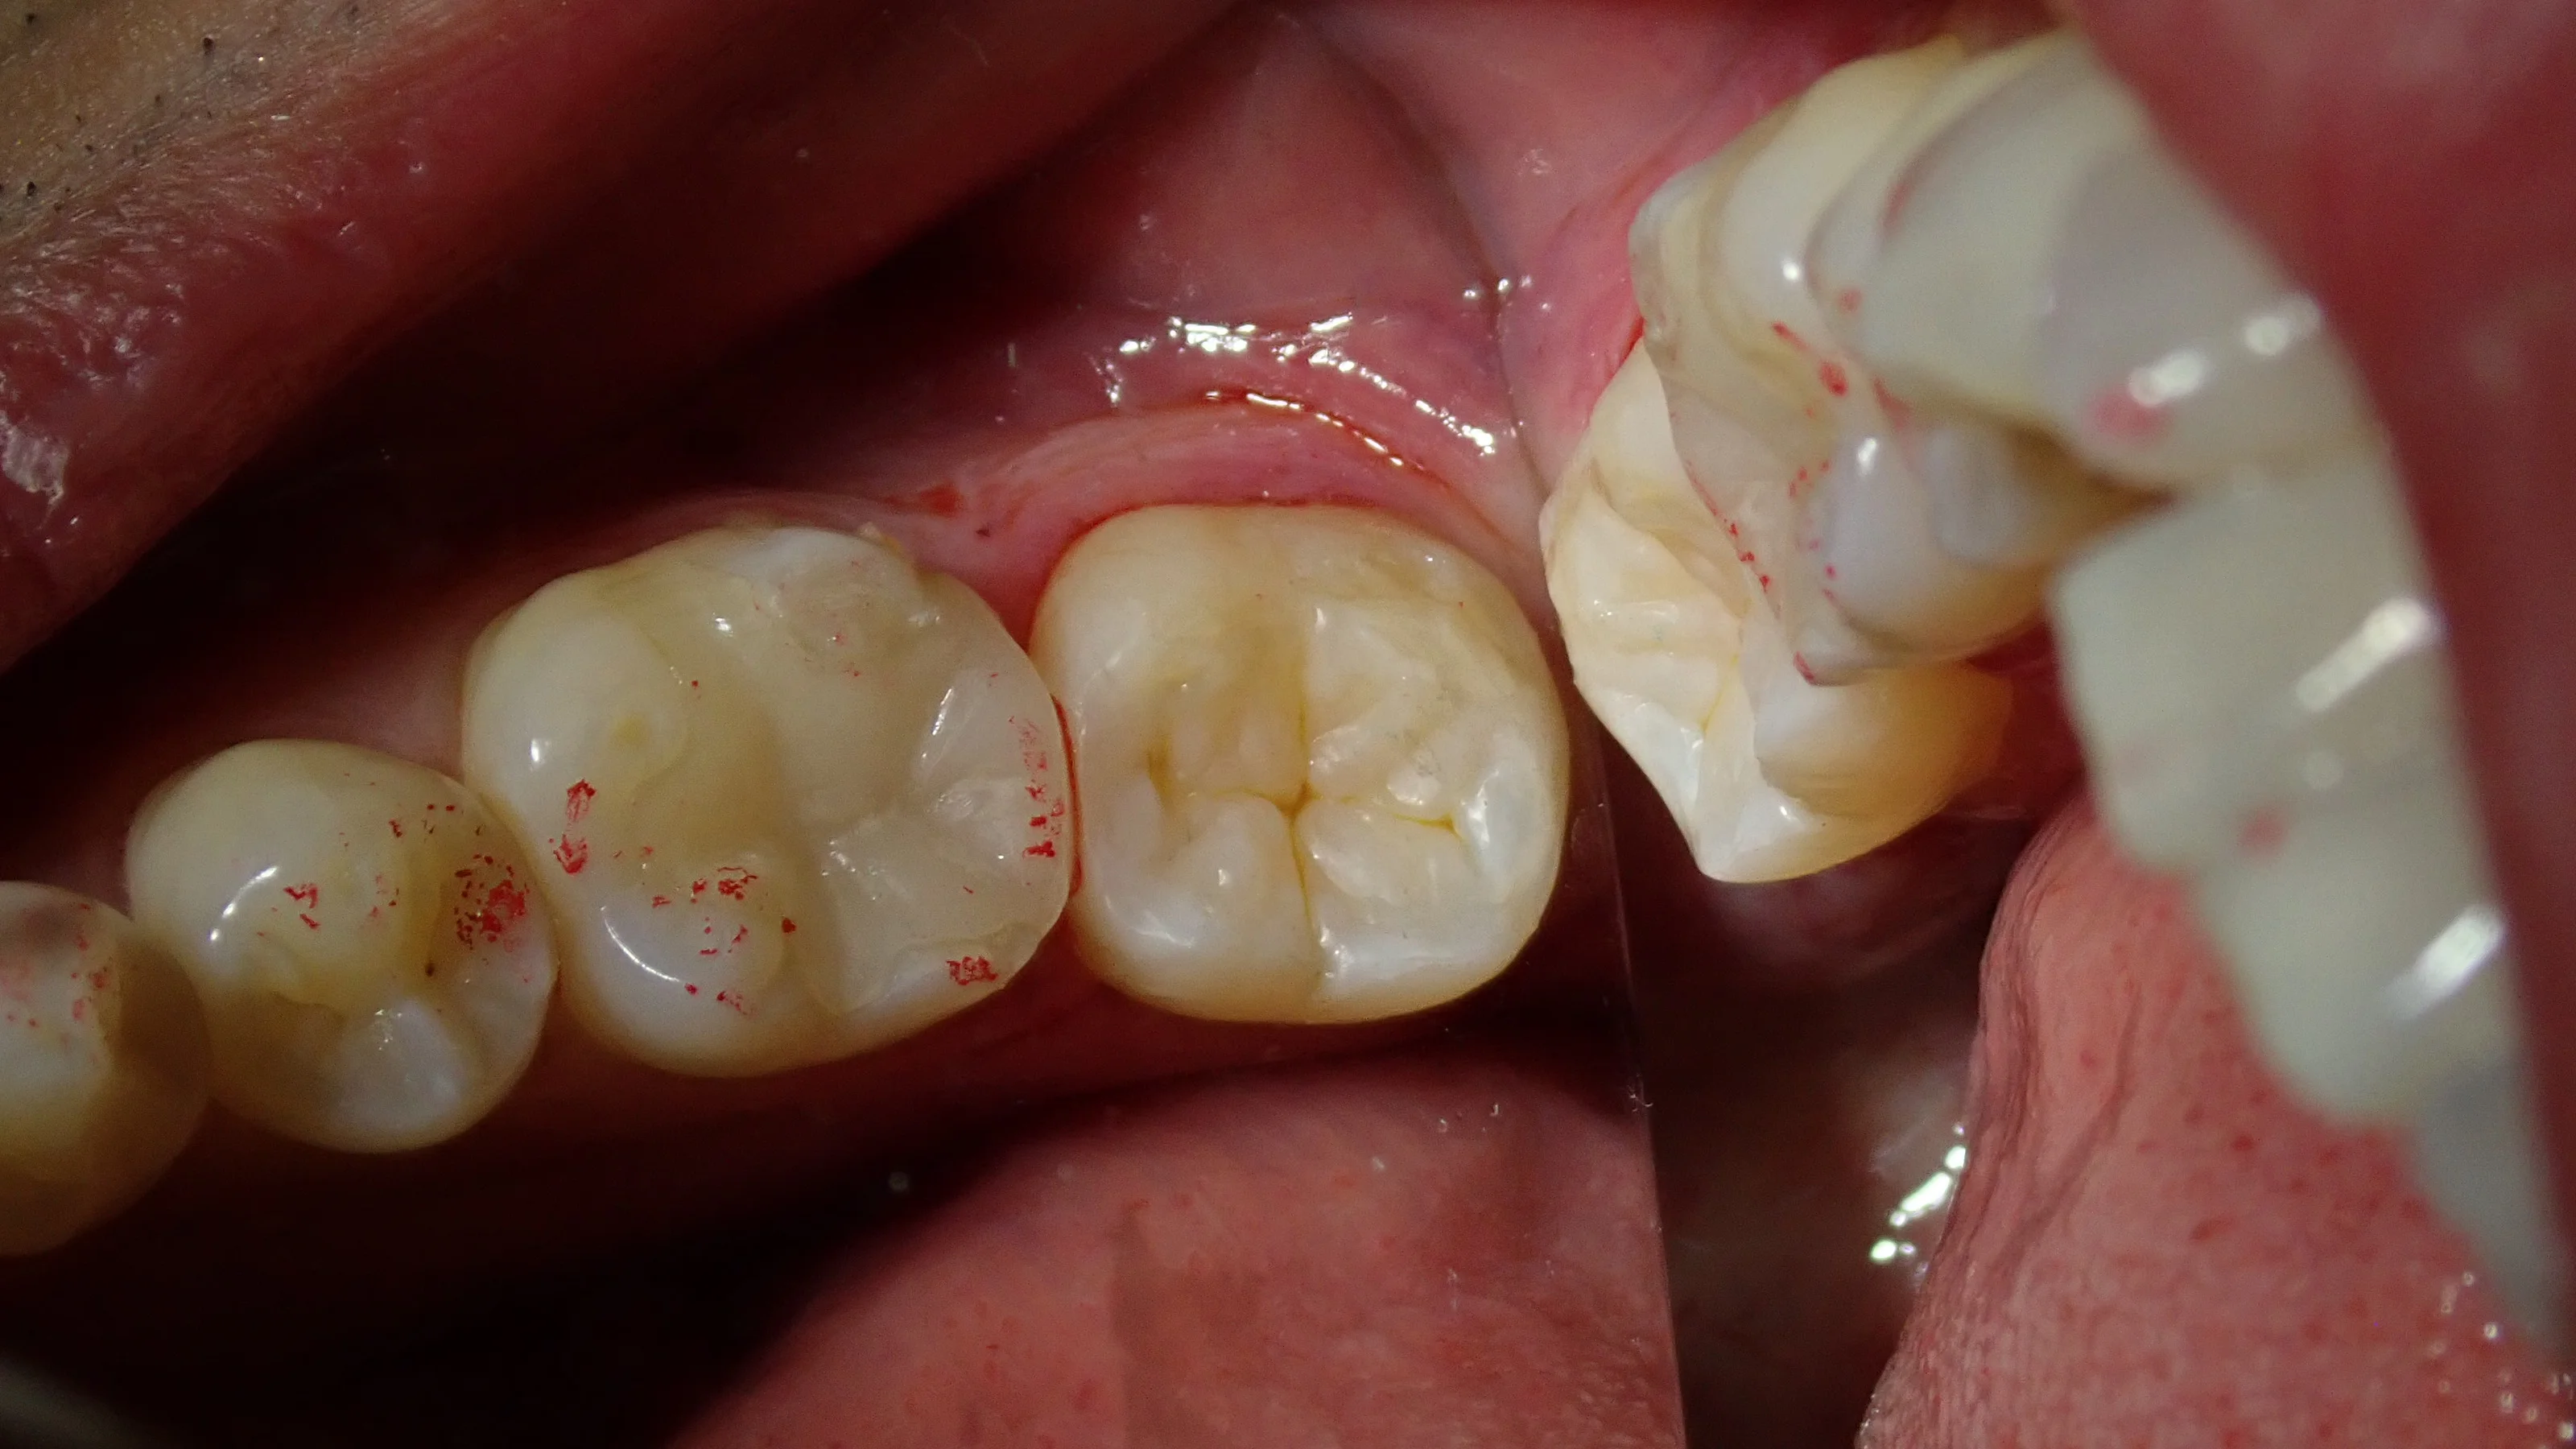

そして、詰め終わったのがこちらです。

咬合面が全く形態が残っていなかった割りには良い感じに出来たのではないでしょうか!?

患者さんには喜んでいただけたので、良かったです!